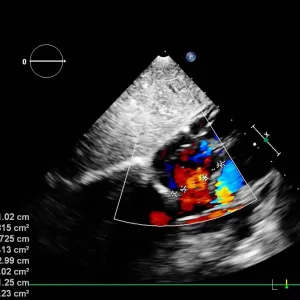

Ecocardiografia – evaluează structura și funcția cardiacă

Ecocardiografie transtoracică – evaluează dimensiunile cavităților cardiace, funcția ventriculară, exclude cardiomiopatii

Ecocardiografie transesofagiană – vizualizează mai bine atriile, exclude trombi intracavitari